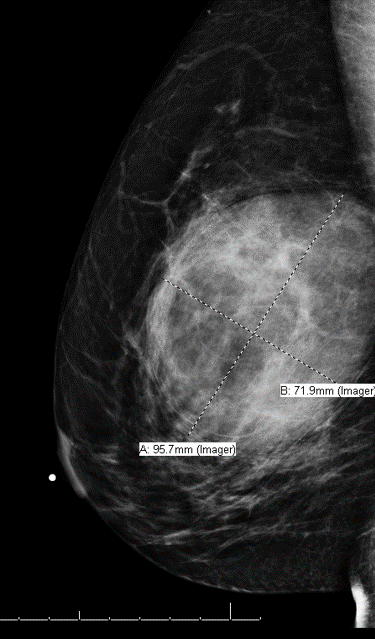

81-year-old female with a remote history of follicular lymphoma was undergoing evaluation for possible disease recurrence when an incidental right breast mass was identified.